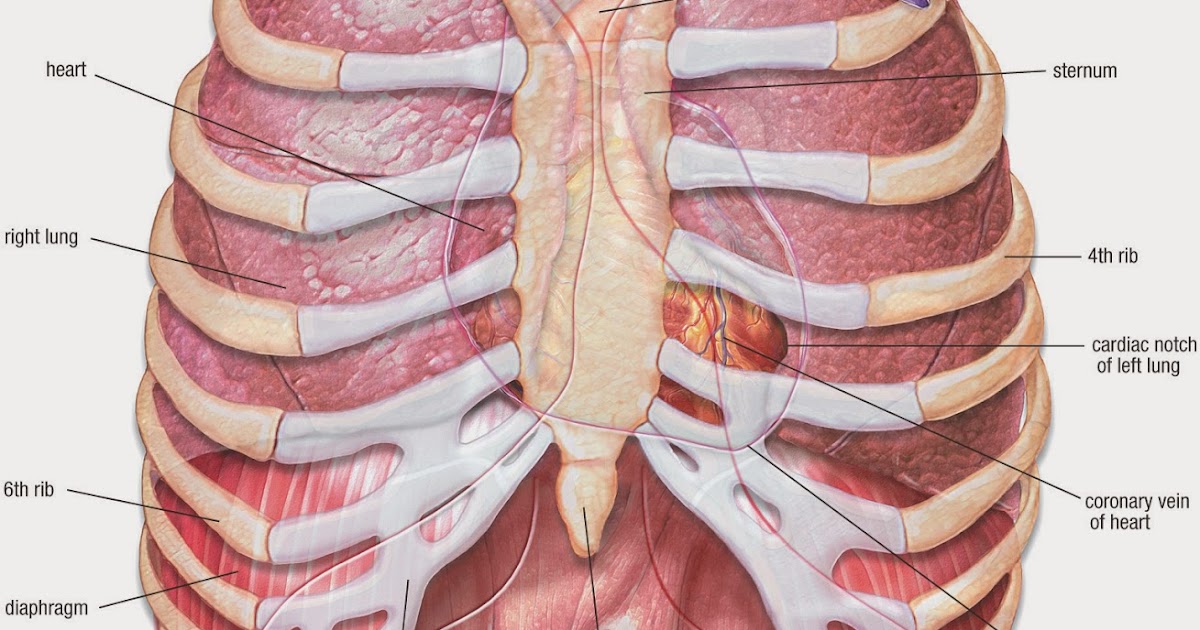

Анатомия Сердца: Расположение и Функции